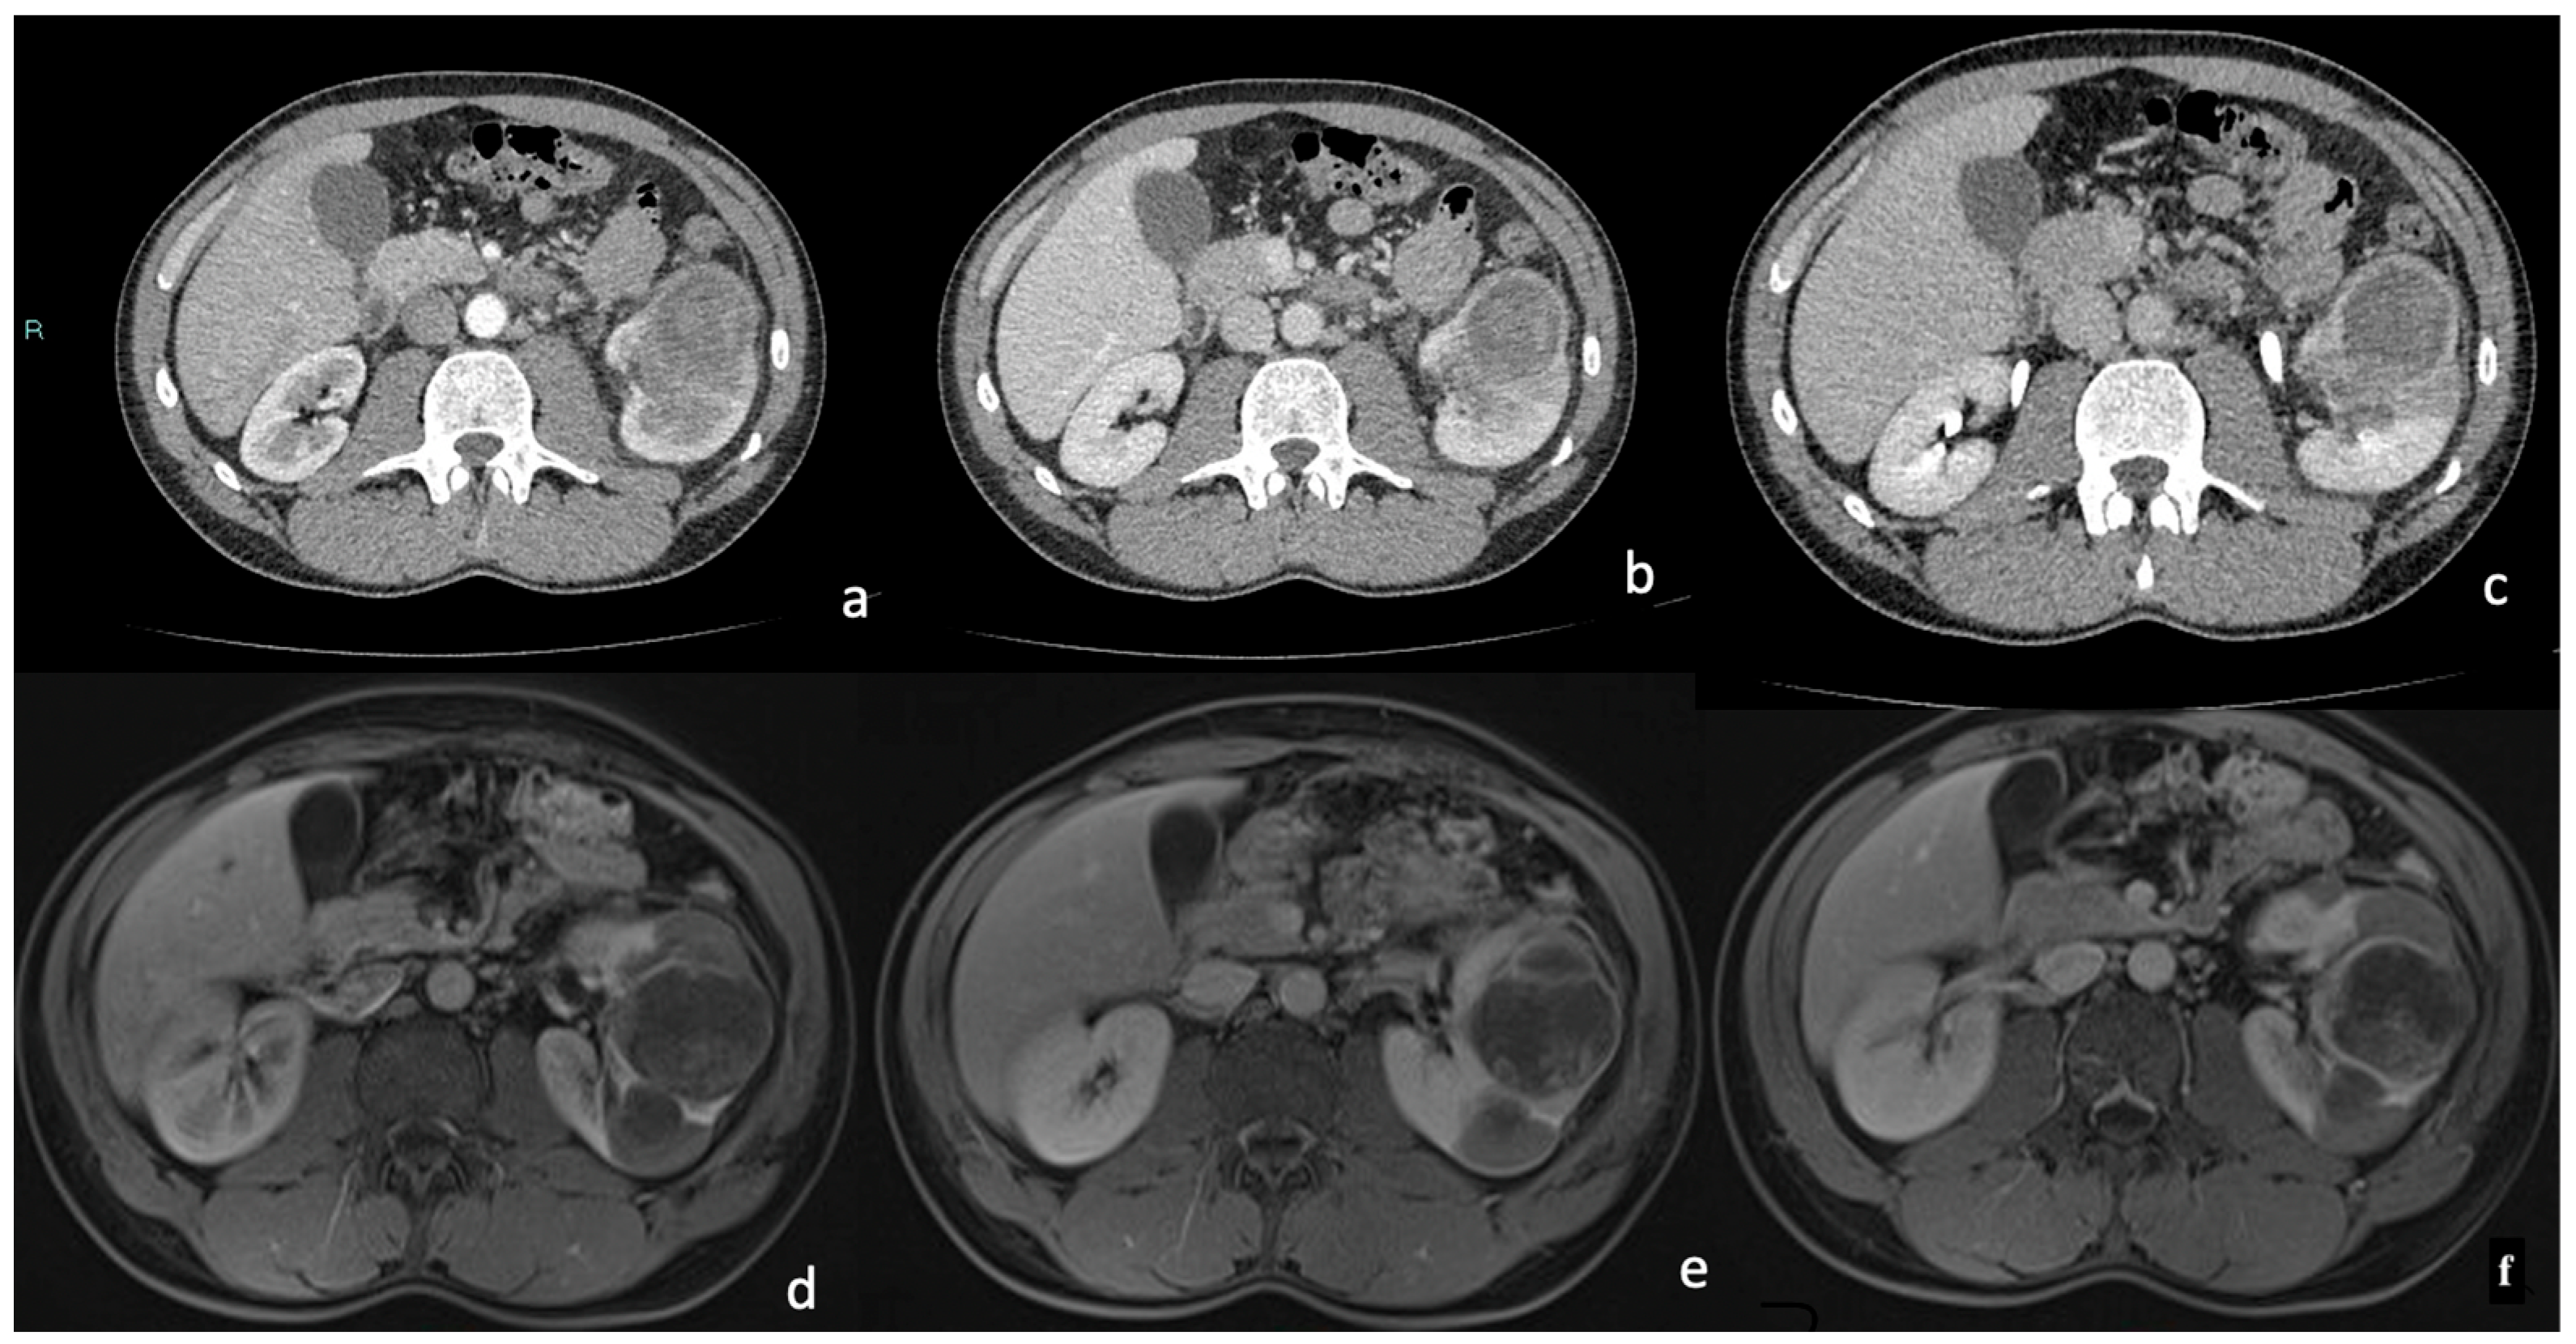

3.3. CT

Density and Contrast Enhancement

- Pre-enhanced phase: 30.3 ± 6.5 HU.

- Arterial phase: 47.2 ± 12.4 HU.

- Venous phase: 64.6 ± 17.3 HU.

- Delayed phase: 61.8 ± 14.5 HU.

3.4. MRI

Signal Intensity, Homogeneity, and Contrast Enhancement